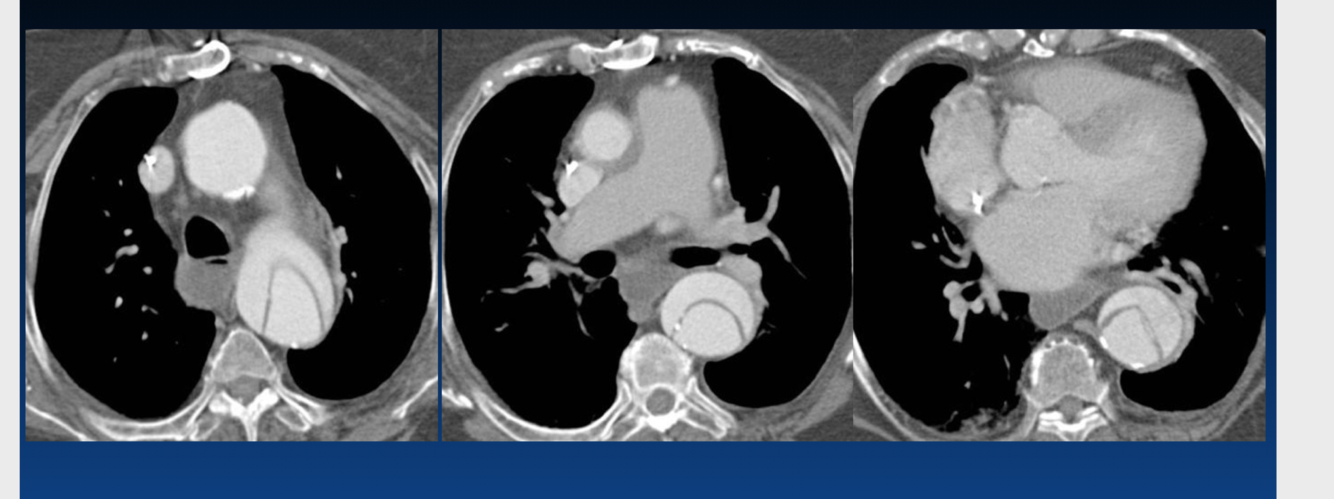

Which type of aortic dissection is treated surgically and which is treated medically?

A: surgical

B: medical